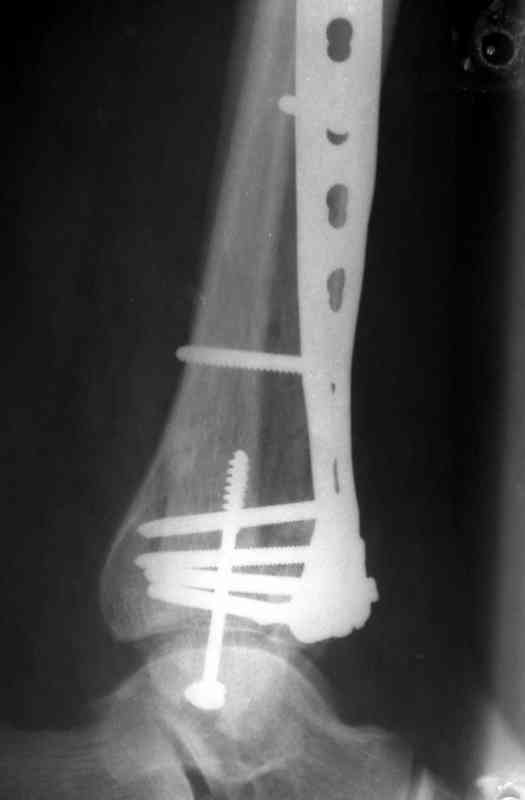

На рентгенограммах типичный перелом пилона по типу С-3. есть опыт до 100 открытых опреаций у нас в клинике. 20 примерно в год. Принцип один -все внутрисуставные переломы нуждаются в открытой репозиции и внутренней стабильной фиксации. При поступлении КТ не надо, так как получается только нагромождение костей. Истинной картины нет. Главное восстановить длину малоберцовой кости - это ключ к успеху. При поступлении меньше всего надо думать о сосудистых расстройствах, т.к. сама операция и репозиция даже сначала частичная даёт улучшение сосудитых нарушений. Причём очень быстро. Операция в 2этапа. При поступлении доступ позади наружной лодыжки, причём обязательно. После этого репозиция малоберцовой кости и фиксация пластиной 1/3 трубки под винт 3,5. Дренаж и любой аппарат наружной фиксации. Затем после спадения отёка на 5-7-10 день аппрат снимается и дугообразный разрез спереди от медиальной лодыжки 10-12 см. Главной чтобы расстояние между 1 и вторым разрезом было не меньше 7-8 см. Тогда не будет некрозов лоскутов. Таранная кость используется как матрица на неё укладываются отломки и фиксируются пицами. Ренг-контроль. Отломки лежат все отдельно, но ничего не высыпется. При переломах С-3 всегда нужна костная пластика (из крыла). Фиксация пластиной лист клевера простой или LCP. Гипс не нужен. Дренаж до 48 часов. Операция длится 3-4 часа обязательно без жгута. Посылаю примерно такой же случай.

Посылаю результат лечения предыдущего больного через год.

С уважением Дрягин